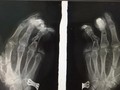

BS. Nguyễn Hoàng Quân - Khoa Phẫu thuật Chi trên và Y học thể thao, Bệnh viện Hữu nghị Việt Đức - cho hay: Ngay sau khi tiếp nhận bệnh nhi, các bác sĩ đã nhanh chóng thăm khám xác định bé bị tổn thương phức tạp dập nát bàn tay trái, cụt chấn thương ngón II, III, đứt gân gấp sâu ngón IV, trật hở khớp bàn ngón III. Các bác sĩ đã tiến hành cắt lọc, găm kim, nối gân, sửa mỏm cụt cho bệnh nhi.

![]() |

Bác sĩ kiểm tra phim chụp Xquang của bệnh nhi (Ảnh - BVCC) |

Sau 4 ngày phẫu thuật, vết thương của bé đã khô, ngón tay 3,4 hồng hào. Bé đang tiếp tục được theo dõi và điều trị tại Khoa Phẫu thuật Chi trên và Y học thể thao, Bệnh viện Hữu nghị Việt Đức.